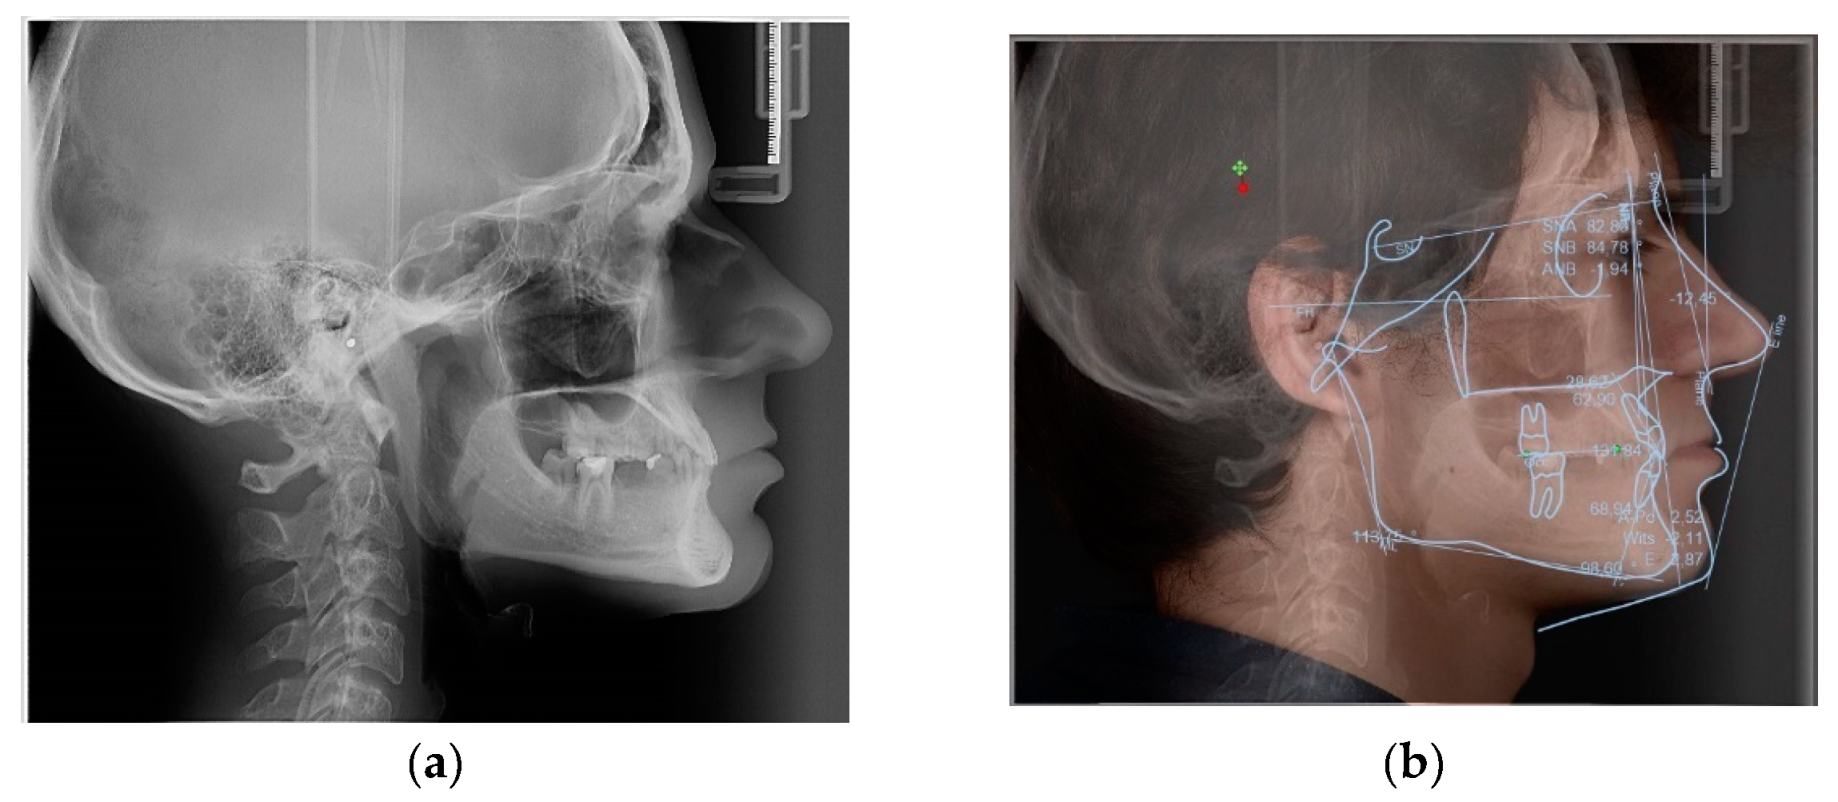

- Preprosthetic orthodontic treatment